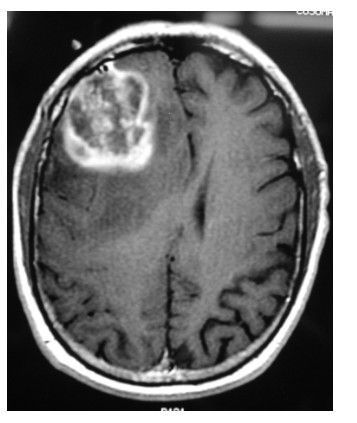

Основным методом диагностики глиобластомы является нейровизуализация — снимки мозга с помощью томографических методов: магнитно-резонансной и компьютерной томографии (МРТ и КТ).

МРТ — наиболее информативный способ, который позволяет точно определить размеры, форму и распространение опухоли, особенно с контрастом на основе Гадолиния: глиобластома выглядит как яркий очаг с отёком вокруг. Метод также подходит для выявления опухолей спинного мозга.

Глиобластома на МРТ [21]